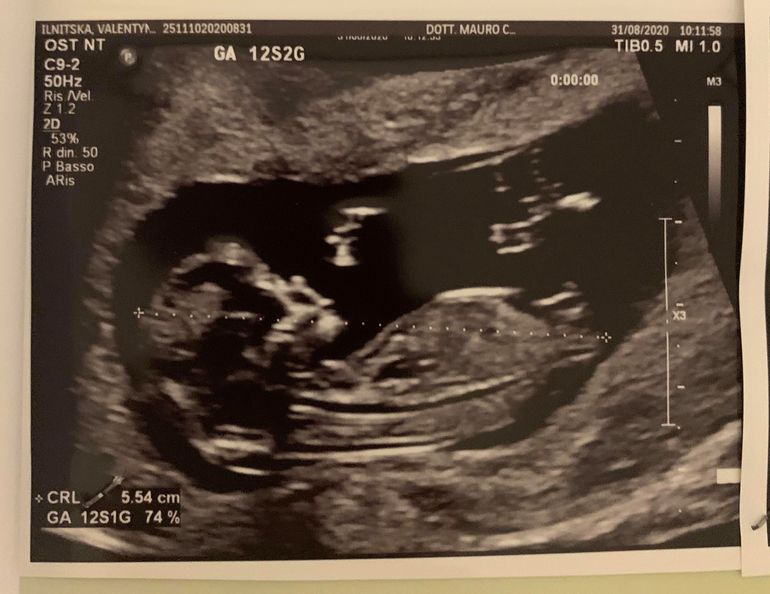

Девочки, дождалась я скриннингового узи наконец то! Так переживала, так нервничала, аж проснулась гораздо раньше и в потолок смотрела. В итоге все у нас в порядке! Носовая кость есть, ТВП 1.4мм, КТР 5.54 см, идет день в день по М несмотря на О на 17 дц (кто помнит, в 7 недель отставал на 5 дней, как же я напереживалась), а сейчас не то что по О догнал, а и по М догнал! Как же я счастлива! 😍 Вначале узи вообще не двигался, такое чуство что спал, а потом как расшевелился, такие танцы вытанцовывал, казалось сейчас выпрыгнет))

Узист сказал, что для пола рано пока, предположил мальчика, но очень не уверенно, когда включил 3д то там действительно чтото выпирало между ножек, но я не знаю как должно быть. Сегодня же буду делать самый базовый НИПТ, его делают 48 часов с момента как материал попадает в лабораторию, так что в среду-четверг будет уже окончательный ответ. А тем времнем есть тут спецы по узи предположить?